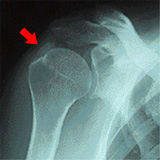

診断結果ですが、レントゲンを見ながら

先生に「石がありますね」と言われました(゚Д゚;)

棘上筋(きょくじょうきん)の上に石灰化した石があるそうです。

結構、時間が経過していないと、こうはならないそうで、

「随分我慢してたんじゃない?」と言われました。

ちょうど↓のような状態でした。結構大きいですがよくあるらしいです。

※画像は日本整形外科学会様からお借りしました

腕の可動域には問題がないため、

痛み止めの注射を打ち、あとは1日1回の「特別な湿布」で

様子を見ることにしました。

特別な湿布とは、「ジクトルテープ」という湿布のことなのですが、

身体のどこに貼っても、皮膚からゆっくり吸収され、血管内に取り込まれると、

内服したのと同じよう効果が得られるそうです。